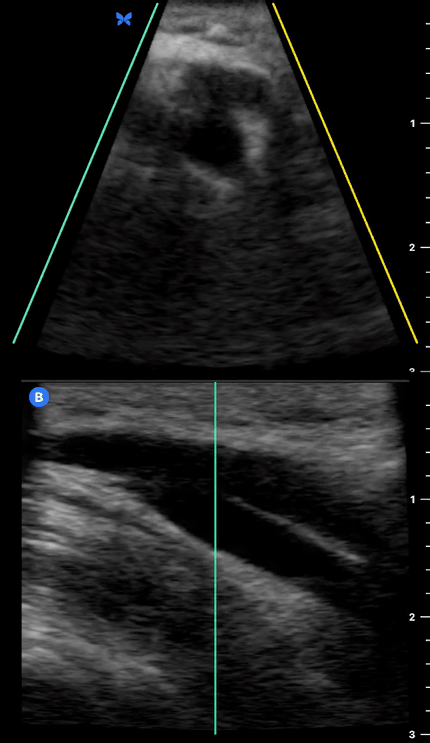

Distal cephalic vein in short axis, cross-section view. The vein is tracked from the wrist to proximal forearm and the antecubital fossa.

Distal basilic vein tracked proximally in cross-section view. On compression, notice the deeper lying brachial vein and artery (pulsatile).

Distal cephalic vein tracked proximally in both planes.

Cephalic vein at the antecubital fossa in both planes.

Basilic vein tracked proximally in both planes.